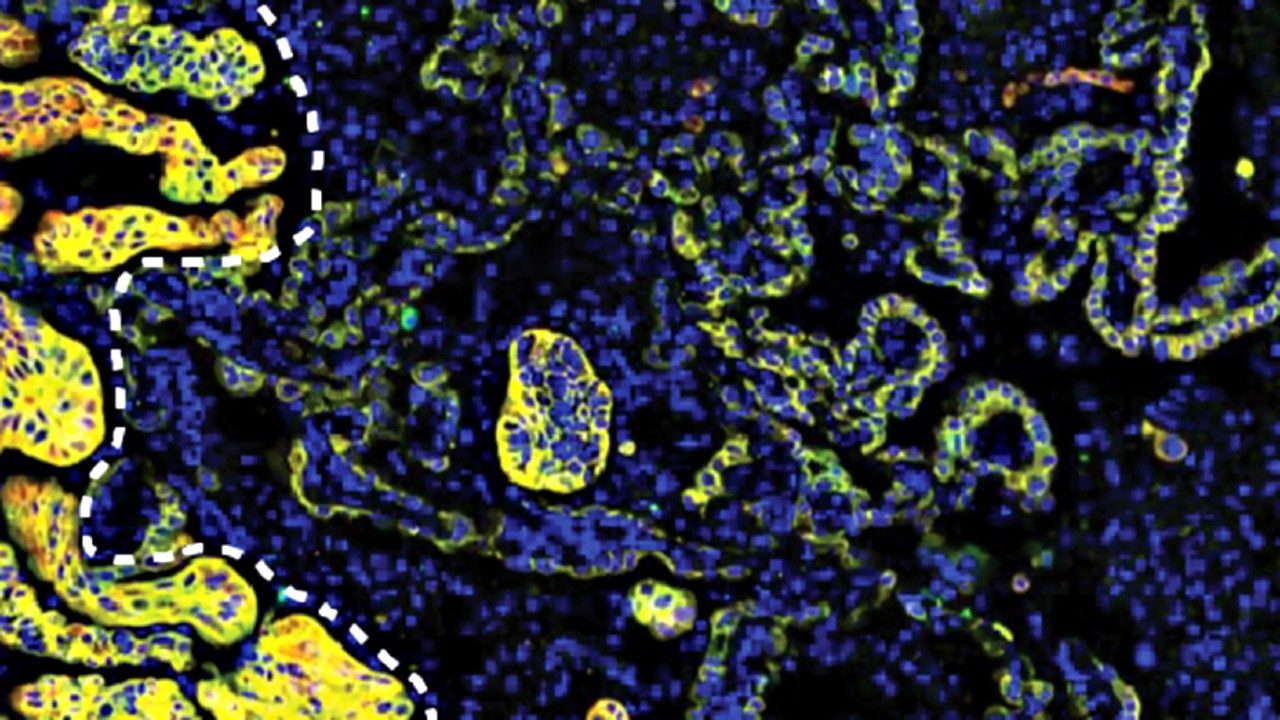

Allison Institute and Institute for Data Science in Oncology blend spatial biology efforts by appointing new member

The James P. Allison Institute™ and the Institute for Data Science in Oncology (IDSO) at The University of Texas MD Anderson Cancer Center today announced the appointment of pioneering computational biologist and data scientist Linghua Wang, M.D., Ph.D., to roles within each institute.

Building on Wang’s previous work and collaborations at MD Anderson, these appointments will allow her to expand the impact of her research...